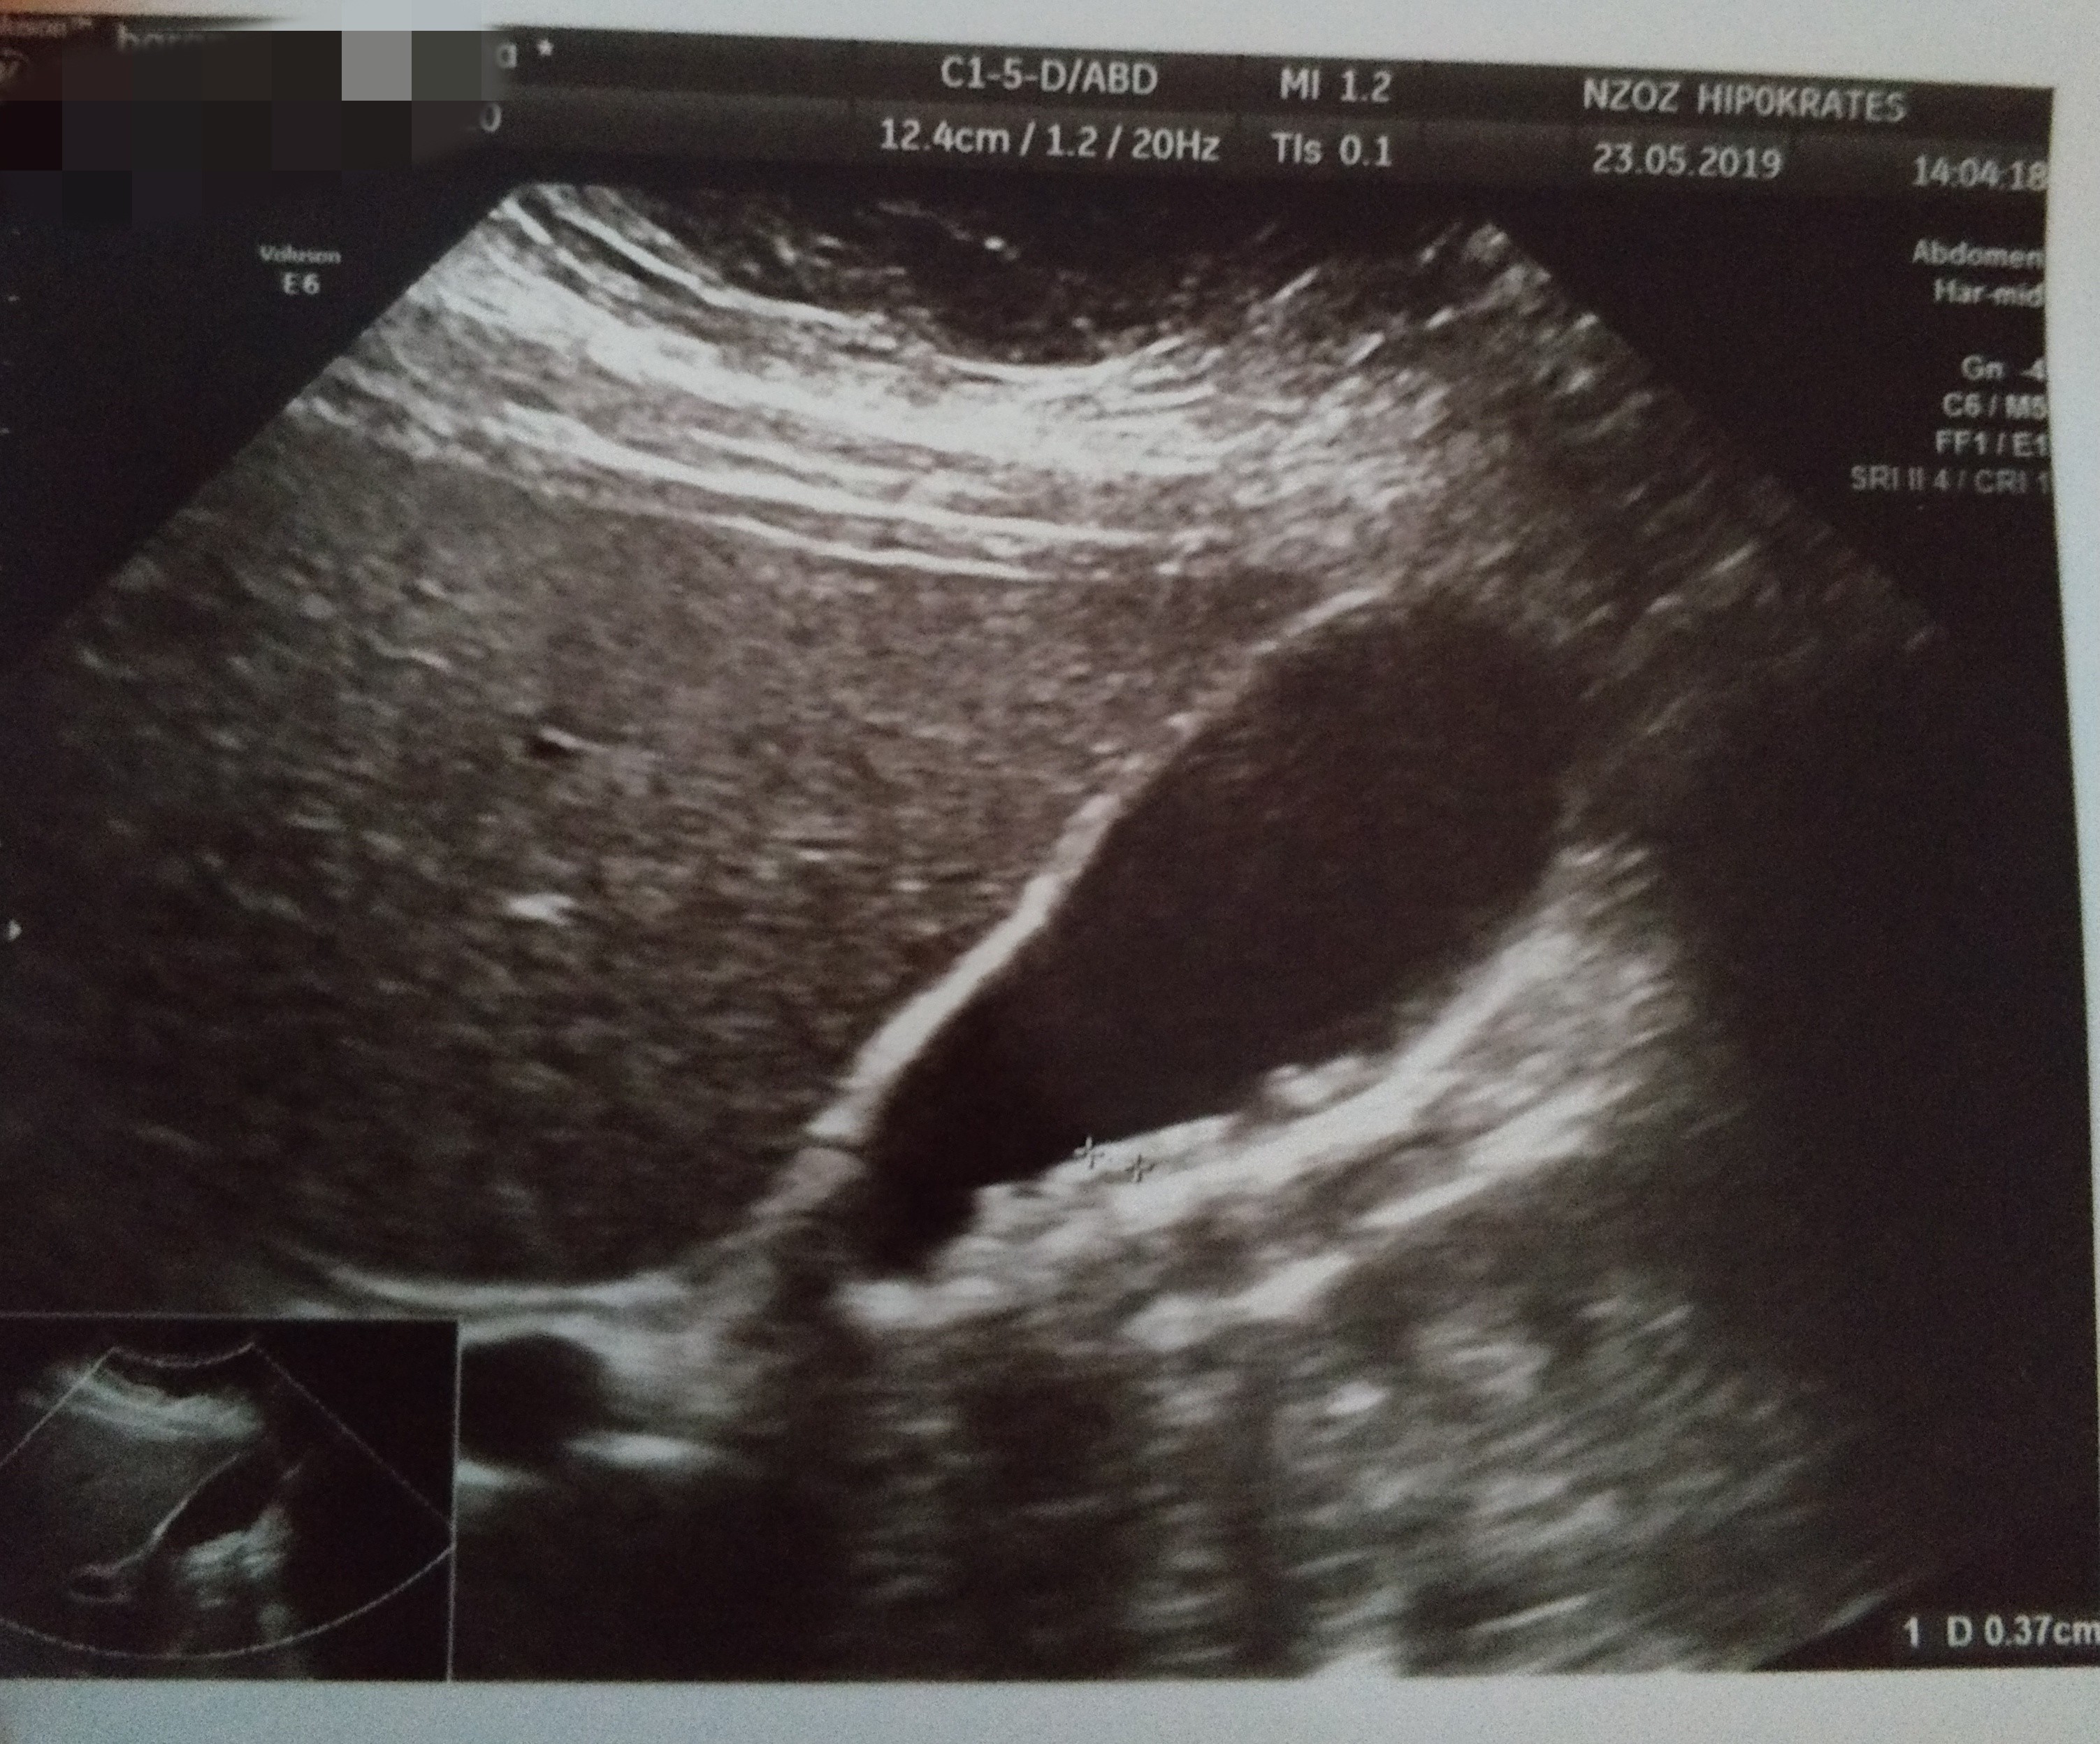

Jestem dzis po Usg brzucha. I juz nie musze isc na gastroskopie. Mam diagnoze. Bardzo liczne kamienie w woreczku zolciowym o wielkosci od 4 do 10mm.

Przedstawiam wam moich niechcianych lokatorów..

IMG_20190523_210812.jpg